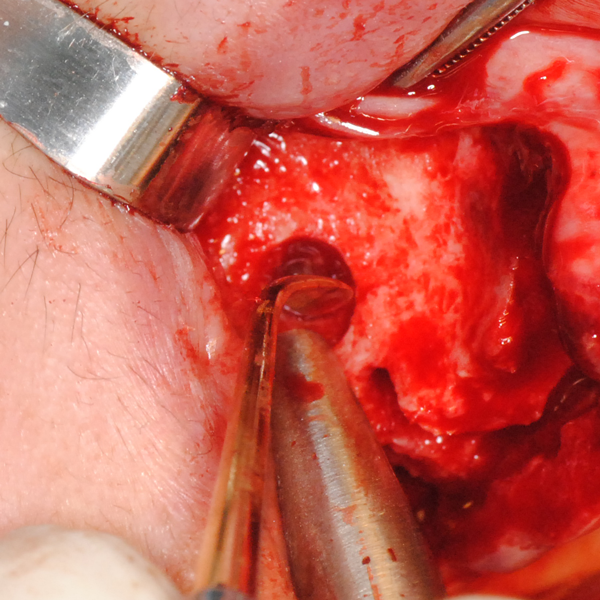

Отворен максиларен синус в началото на интервенцията. Случаят е интересен със следното - твърде атипична форма на трепанационния отвор. На какво се дължи на това - на лошо планиране на оперативния достъп или на нещо друго? Дължи се на факта, че отначало въпросната намеса беше планирана като балонен синуслифт; за съжаление обаче мембраната на синуса се разкъса и надуването на балона стана невъзможно.